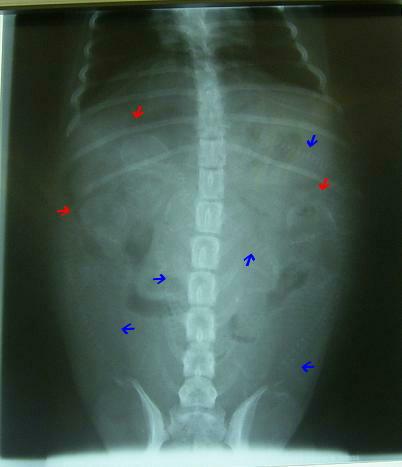

レントゲンは2方向から2枚撮りました。

昨日のレントゲンは何だった?

と思う程鮮明な画像でハッキリと

5頭確認

しました。

そして、エコーでも心臓の動きをしっかり確認してきました。